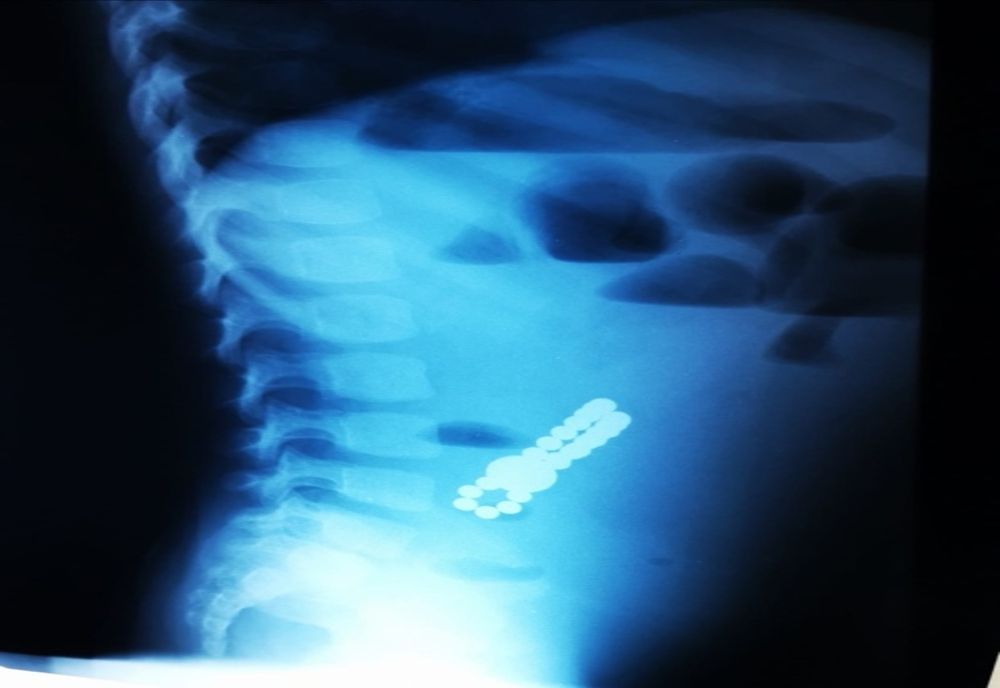

Dr. Adriana Constantineanu, medic specialist în chirurgie pediatrică atrage atenția asupra pericolului din spatele jucăriilor cu magnet. Acestea îi pot distra pe copii și pot fi fascinați de multitudinea de culori vii care îi duce cu gândul pe cei mici la bomboane, înghițindu-le.

„Acești magneți sunt foarte puternici, iar ingestia lor poate duce la probleme gastrointestinale grave. Odată înghițiți sunt atrași unul spre altul chiar dacă se găsesc în secțiuni diferite ale tubului digestiv. O ansă intestinală prinsă între acești magneți se poate perfora ducând la tratament chirurgical de urgență. În secția noastră, de la începutul anului s-au prezentat trei cazuri, două fete și un băiat, cu vârste cuprinse între 2 și 4 ani.

Aceștia au suferit perforații la nivelul intestinului subțire și au necesitat intervenții pentru îndepartarea porțiunii de intestin afectate”, a precizat dr. Adriana Constantineanu.